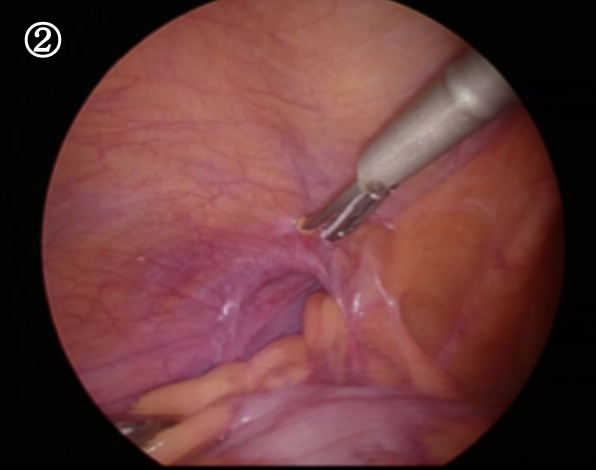

ソケイヘルニアをおなかの内側から見た写真です。ソケイ部に開いた大きな穴におなかの中の脂肪や腸が入り込んでいます。

まずはこれを引き出すことから始まります。これを引き出すと・・・・・